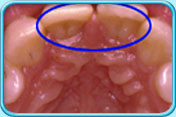

圖中所見是上排兩顆正門牙於鑲配牙冠前的外觀。治療前。

圖中所見是上排兩顆正門牙於鑲配搪瓷牙冠後的外觀。治療後。